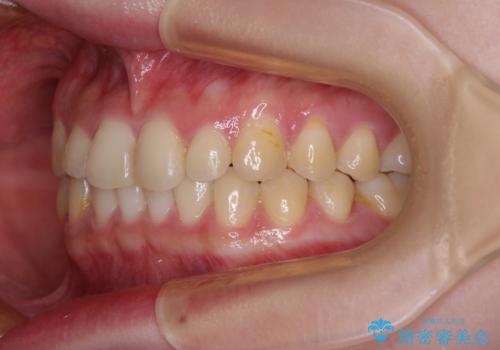

治療途中の奥歯と矯正治療の後戻り インビザライン・ライトによる矯正治療

- 根管治療を行ったままの奥歯と、矯正治療の後戻りを気にして来院された患者様です。

根管治療された歯に症状はなく、オールセラミッククラウンにて補綴治療を行うこととしました。

矯正治療の後戻りは軽微であったため、インビザラインの簡易パッケージであるインビザライン・ライトを用いて歯列を整えることとしました。

クラウンはよりよい咬み合わせで装着したいため、インビザラインを1セット使用して概ね歯列を整えた時点で補綴治療を行い、その後仕上げの矯正治療を行いました。